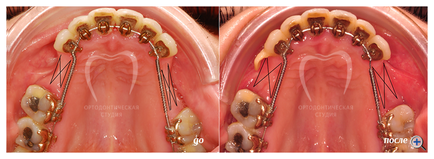

Метод розщеплення щелепної кістки

Збільшення ширини альвеолярного відростка верхньої щелепи (альвеолярної частини нижньої щелепи) методом розщеплення кістки дозволяє уникнути забору аутотрансплантата, при цьому використовується матеріал поміщається в глибину губчастого шару кістки, що в значній мірі покращує перебудову і заміщення матеріалу кісткою.

Втручання проводять під місцевою анестезією з розщепленням материнської кістки щелепи приміщенням трансплантата всередину з'явився простору. Найбільш поширена операція розщеплення кістки, коли розщеплюється і розсувається вузький гребінь щелепи з подальшою установкою імплантата. Тривалість післяопераційного періоду залежить від методики кісткової пластики. Для того щоб він пройшов якомога швидше і комфортніше, необхідно дотримуватися рекомендацій, які вам дасть стоматолог. Такі ускладнення, як розбіжність країв рани і вихід через ясна аутотрансплантата, частіше зустрічаються у курців, тому на період лікування пацієнту краще відмовитися від куріння. Небажано також носіння знімного тимчасового протеза, що спирається на аутотрансплантат.